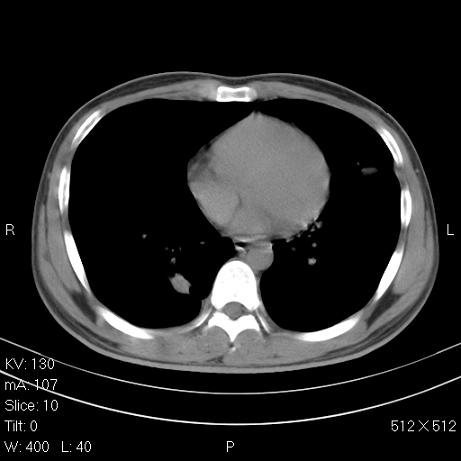

标题: CT7171B:补充治疗后2周复查 [打印本页]

标题: CT7171B:补充治疗后2周复查

治疗后2周复查,请讨论

结合以前的ct片,还是考虑肺挫伤,吸收多了。

支持:创伤性湿肺。现肺挫裂伤(出血 积气)大部分吸收。建议继续治疗!

结合以前的ct片,支持创伤性湿肺。现大部分吸收。

支持:创伤性湿肺、肺挫裂伤。现肺挫裂伤(出血、渗出、液气腔)大部分吸收。建议继续治疗!

支持:创伤性湿肺、肺挫裂伤。现肺挫裂伤(出血、渗出、液气腔)大部分吸收.

结合老片支持创伤性湿肺、肺挫裂伤。

经治疗后病灶明显吸收,考虑创伤性湿肺、肺挫裂伤